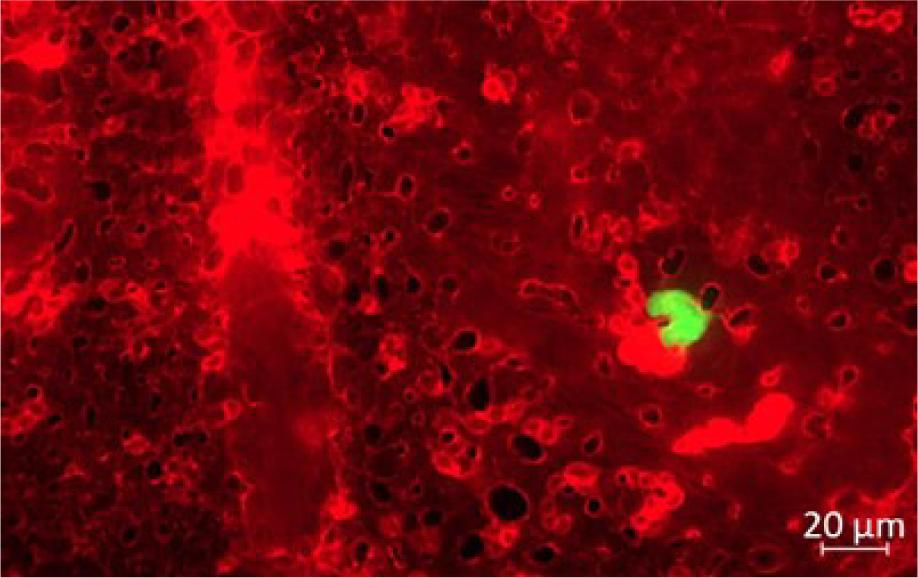

Fig. 2.

Stained D-17 cell located intravascularly in the lumen of the CAM blood vessel. Scale bar 20 μm